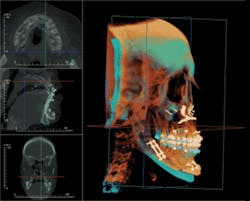

All CBCT manufacturers include OEM (Original Equipment Manufacturer) software with their machines. This software varies with the specific units, but generally includes a method of viewing the scan in an interactive frontal, sagittal, and coronal mode known as Multi-Planer Reconstruction (MPR). Each scan is reviewed first by browsing through the cross sections in all three planes and noting any findings, with particular attention paid to the diagnostic condition of interest (Figure 1).

Specialized orthogonal cross sections, such as panoramic planings, are performed to elicit a more directed view of areas of interest. The Hounsfield density measures the relative density of the involved structures and offers insight into the nature of the lesion. Most OEM software includes a 3-D viewer which can be applied to the scan to observe the volume of the target and its juxtaposition to other structures. Measuring tools in the software enable precise measurements in both the 2-D and 3-D images. The 3-D images can be cropped to decrease superimposition of adjacent structures — surface rendered to view skin and airway volume — all of which can be rotated for viewing at any angles. Most OEM packages have a function which displays corrected tomographic AP and coronal slices through the temporomandibular joints.

The Anatomage software employs various methods to filter out metallic scatter, producing a highly selective, clean 3-D volume in which structures can be easily selected and isolated for analysis. This process of clean isolation permits views of teeth, airway, temporomandibular condyles, the mandibular complex, and sinuses. Furthermore, it allows volumetric measurement and positional manipulation to formulate surgical or prosthetic projections.